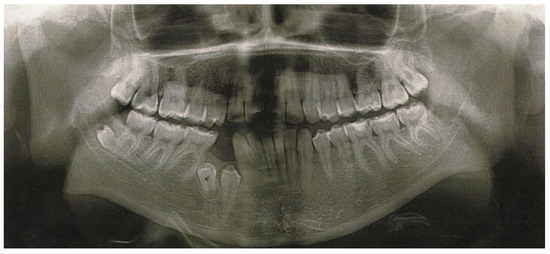

2. Case Report